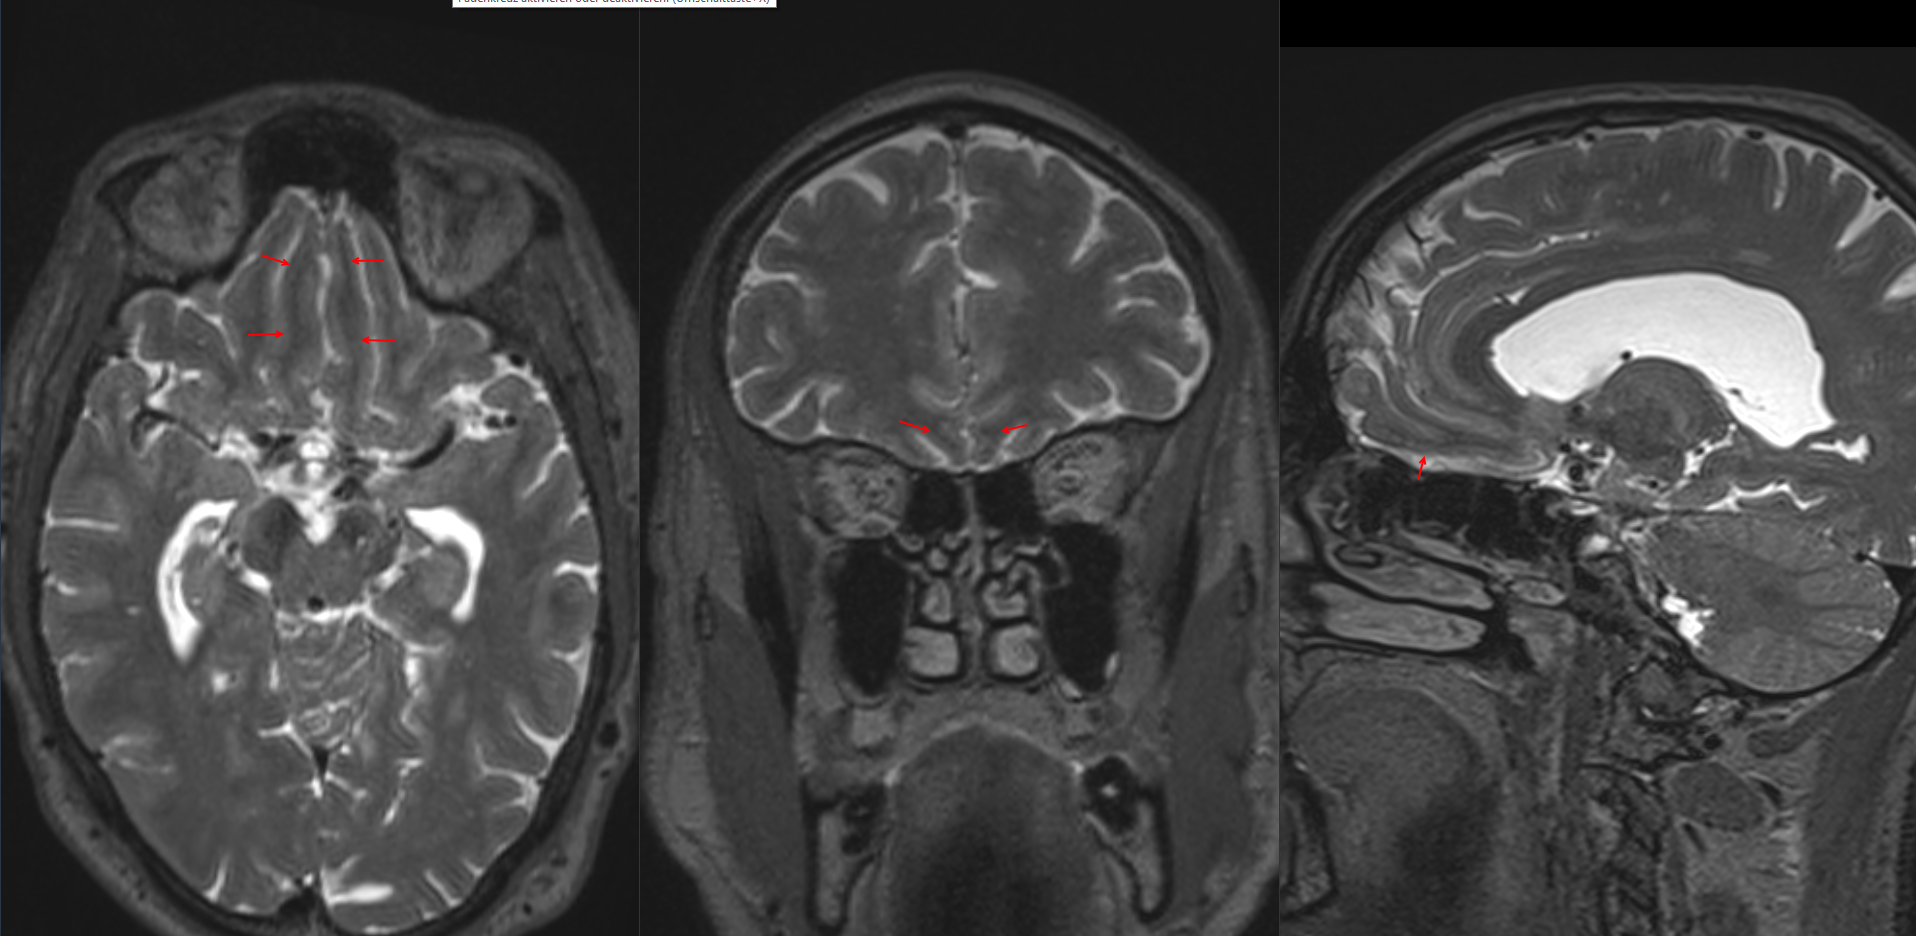

Gyrus rectus im MRI

Darstellung des Gyrus rectus in einer T2 MRI Sequenz im sagittalen, coronalen und axialen Bild.